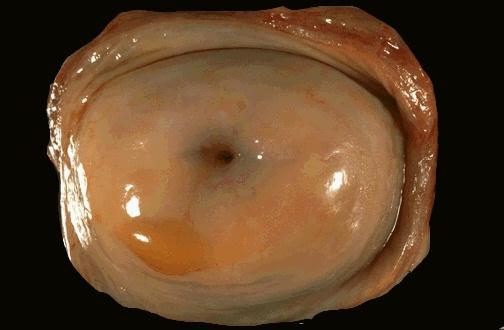

完好的子宫颈图片|

①宫颈管黏膜即子宫颈内膜,有分泌黏液的单层柱状上皮覆盖,上皮在固有层下陷成腺样隐窝,习惯称为子宫颈腺,能分泌黏液,成为白带的主要组成部分;

②在宫颈管内膜表面和腺体柱状上皮下方、基底膜上方有储备细胞,子宫颈图片,具有增生和可以分化为柱状上皮细胞和化生为鳞状上皮的双向分化潜能;

③宫颈外口到阴道穹隆均为复层鳞状上皮覆盖;

④子宫颈管柱状上皮和宫颈外面的阴道鳞状上皮相交界区称宫颈上皮移形带或转化区,两种细胞的交界区位置并非一成不变,随女性体内雌

激素水平的高低、年龄、内分泌、阴道pH值和病理状态不同而可有位置移动。若雌激素水平高,如生育期年龄妇女,移形带向宫颈外口外移,使宫颈管内柱状上皮因外移而暴露在外。